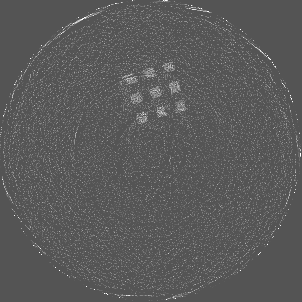

Figure 7 shows a single slice spectral reconstruction of the Mg scaffold. Due to low atomic number of Mg (Z = 12) compared to Ti (Z = 22), the results did not exhibit any significant beam hardening effects. Low energy reconstruction shows good spatial information while high energy ranges are limited by photon noise. In scans involving smaller samples made from low-Z materials like Al or Mg, acquiring low energy quanta in CSM provide high spatial information with minimum or no beam hardening effects. Figure 8 illustrates a single slice spectral reconstruction of the Ti mesh. Similar to the Ti scaffold, streaks are less pronounced in the mid and high energy ranges.